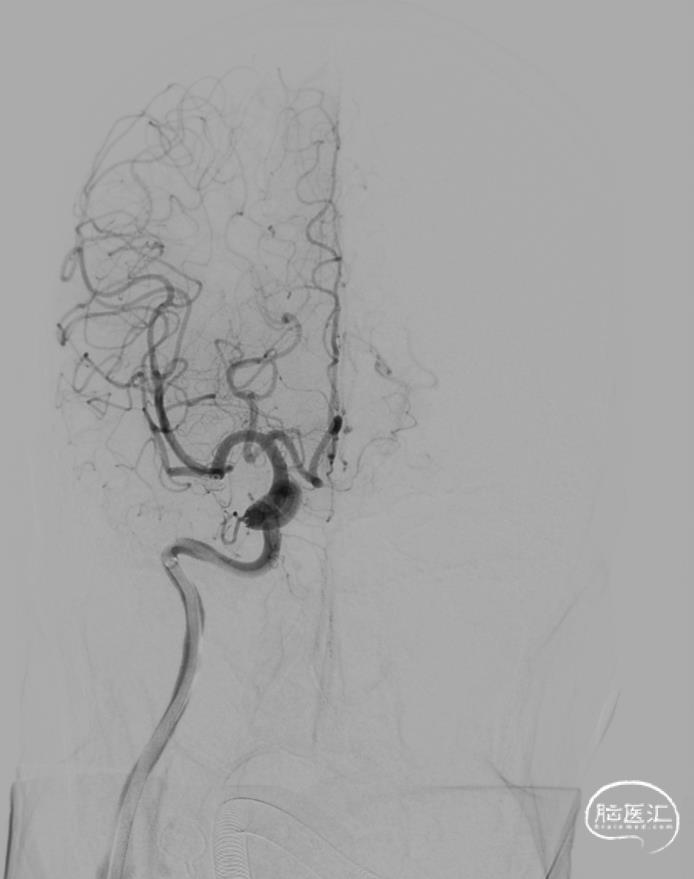

结束前造影。

患者全麻复苏后出室,无神经功能缺损。一切顺利。